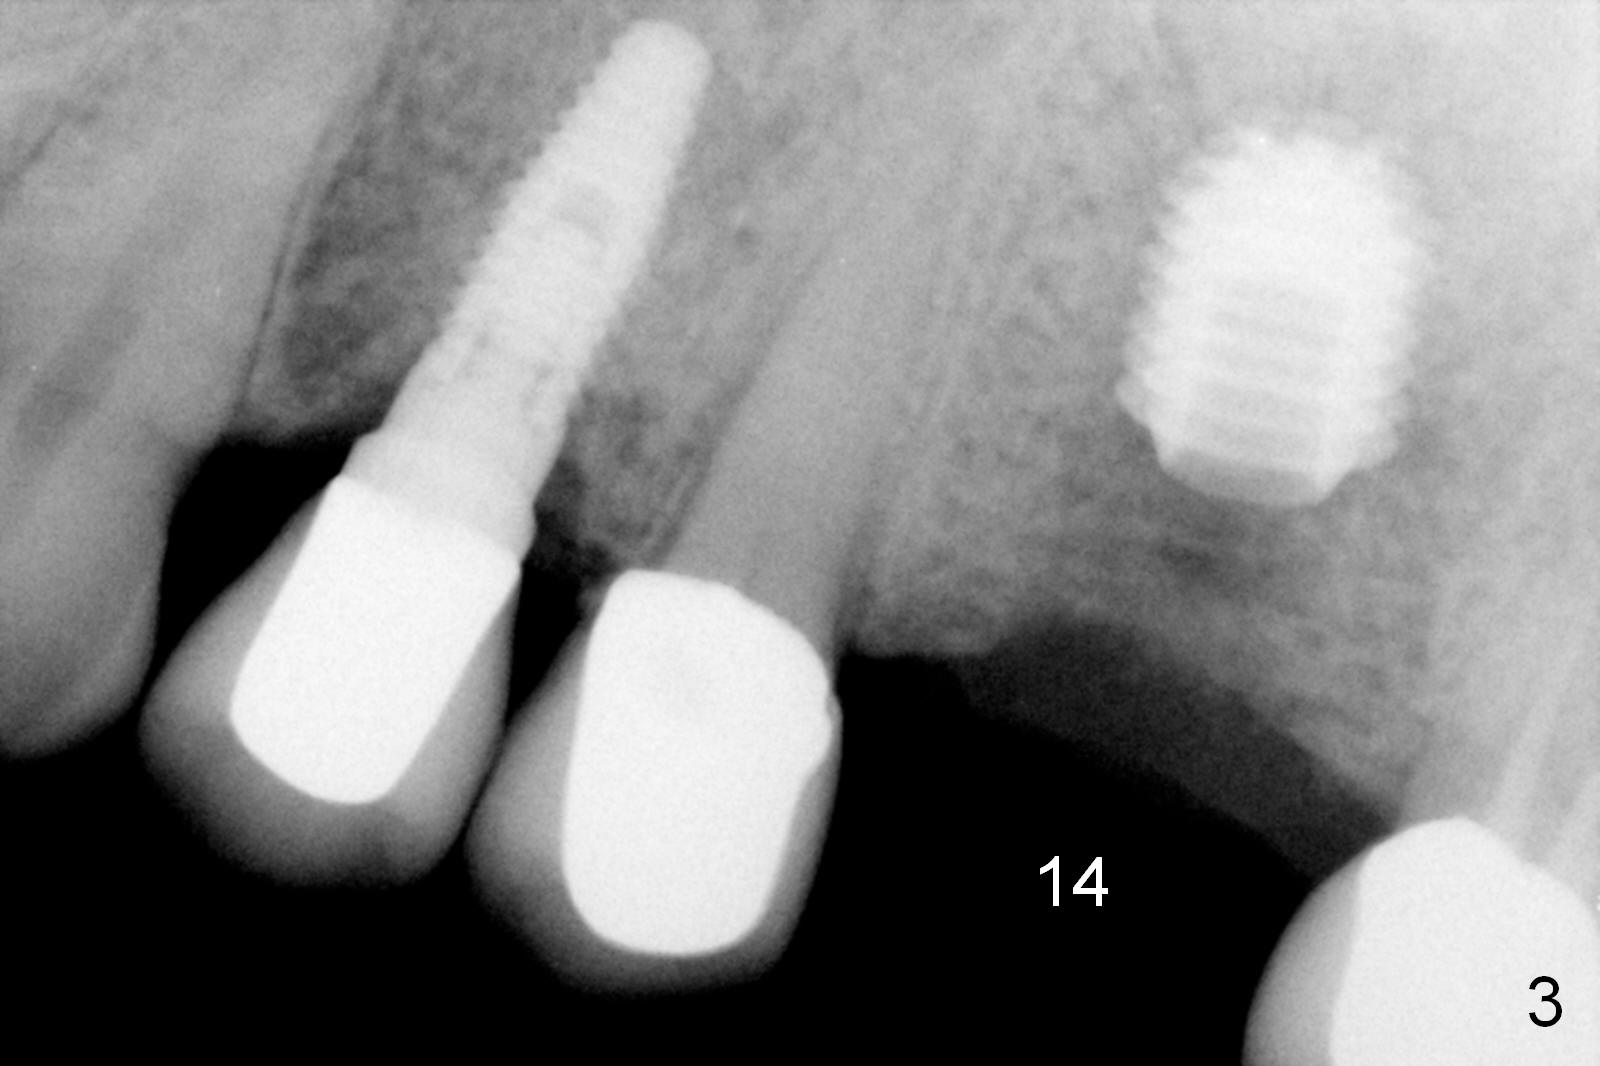

A 73-year-old man returned for recall and had panoramic X-ray taken yesterday. The latter shows no bone loss associated with different types of implants (Fig.1). The implants (relatively small in diameter) and crowns were present at the sites of #3 and 12 when the patient presented to my clinic 6 years ago. His chief complaint was discomfort at #13-15 fixed partial denture (FPD). The tooth #15 seems to be without pathology. To increase its longevity, the FPD was removed (Fig.2), a 5x8 mm Bicon implant (short) was placed at #14 (5 years 11 months post cementation now) and single unit restorations were cemented at #13 and 15 (Fig.3). The occlusal table of the implant crown at #14 is narrow buccopalatally (Fig.4). The occlusal contact of the implant restoration is minimal (Fig.5), which is unfavorable for the weakened tooth (#15). The latter shows sign of failure 7 months post #14 crown cementation (Fig.6 >). The patient refused to accept treatment for #15. Seven months later, the tooth #5 fractured (1st sign of bruxism) and a 5x20 mm cylindrical Tatum tissue-level implant (long) was placed immediately (4 years 5 months in function now). Finally the patient agrees with immediate implant at #15 (7x17 mm tapered Tatum tissue-level implant, large). Follow up is 2 years 7 months post cementation. Ideally 2 implants should have been placed when the FPD was removed. To reduce deleterious effect of bruxism, the last implant was placed with bone expansion at the edentulous area at #2 (5.3x14 mm DIO submerged implant, 1 year 9 months post cementation now). The 2nd sign of bruxism is placement of inlay/onlay on the teeth #19 and 30 (Fig.1). The palatal cusp of the implant crown at #13 remains untreated. The 2 immediate implants at #5 and 15 happen not to have immediate provisional. In all, for a bruxer, an implant does not have to be large or long as long as implant trajectory is correct.